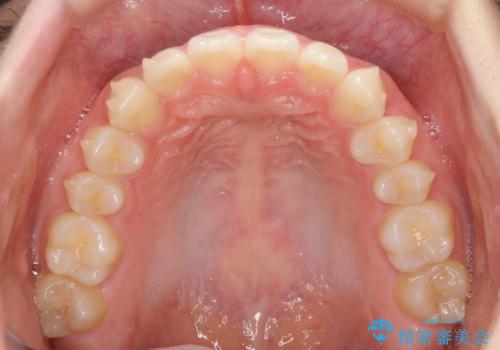

- 上の前歯の隙間を気にして来院された患者様です。

インビザラインにより、隙間を閉じながら、隙間の原因であるディープバイトを改善していくこととしました。

下顎の歯列が強く上顎に咬みこむことで隙間ができてしまうため、マウスピースの保定装置では後戻りのリスクが高くなってしまいます。

そのため、上下ともに前歯の裏側を細いワイヤーで固定し、その上から保定装置のマウスピースを使用していただくこととしました。